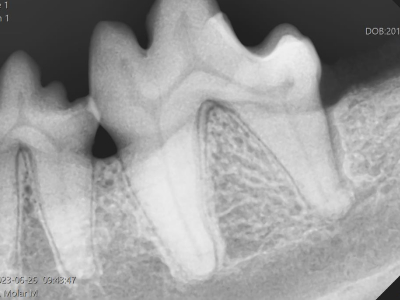

治療前X線

X線を撮ってみると歯の後ろ側の骨が歯周病によりなくなっています。

治療1年後

1年後のX線では見事に骨が再生しています。